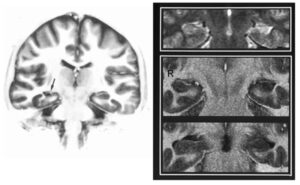

Sviluppo dell’epilessia temporale